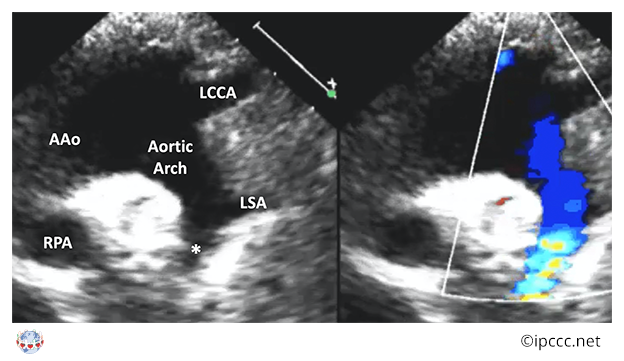

You are here: Coarctation of aorta ⇗ Congenital anomaly of aorta or its branches ⇗ Congenital anomaly of great arteries including arterial duct ⇗ Structural developmental anomaly of heart or great vessels

A congenital cardiovascular malformation in which there is a discrete luminal narrowing of the junction between the aortic arch and the descending aorta.

Coarctation of the aorta generally indicates a narrowing of the descending thoracic aorta just distal to the left subclavian artery. However, the term may also be accurately used to refer to a region of narrowing anywhere in the thoracic or abdominal aorta.

Echocardiogram